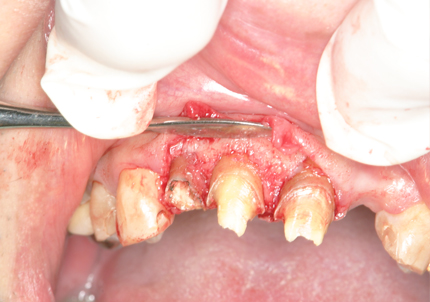

3.歯冠長延長術(2014年11月)

➡ 歯冠長延長術とは・・・歯ぐきや骨の位置を調整して、歯の見えている部分(歯冠)を意図的に長くする治療。歯ぐきがかぶって歯が短く見える審美的な問題、歯周病治療や補綴治療を成功させるための前処置等として行われる。

【 縫合 】